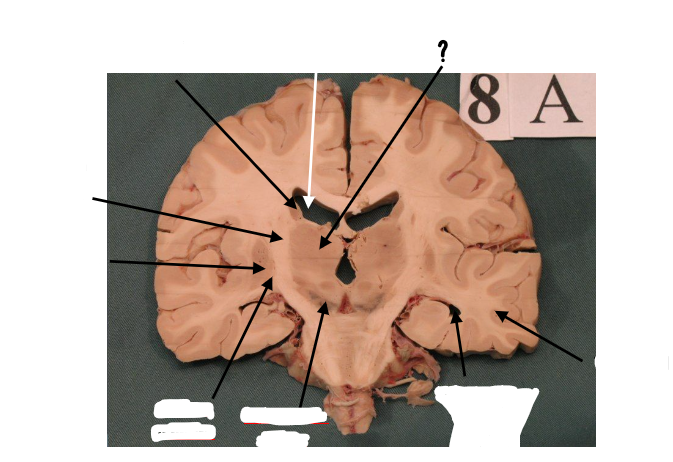

body of caudate nucleus

lateral ventricle

thalamus

internal capsule

putamen

globus pallidus

substantia nigra

inferior horn of lateral ventricle

temporal lobe